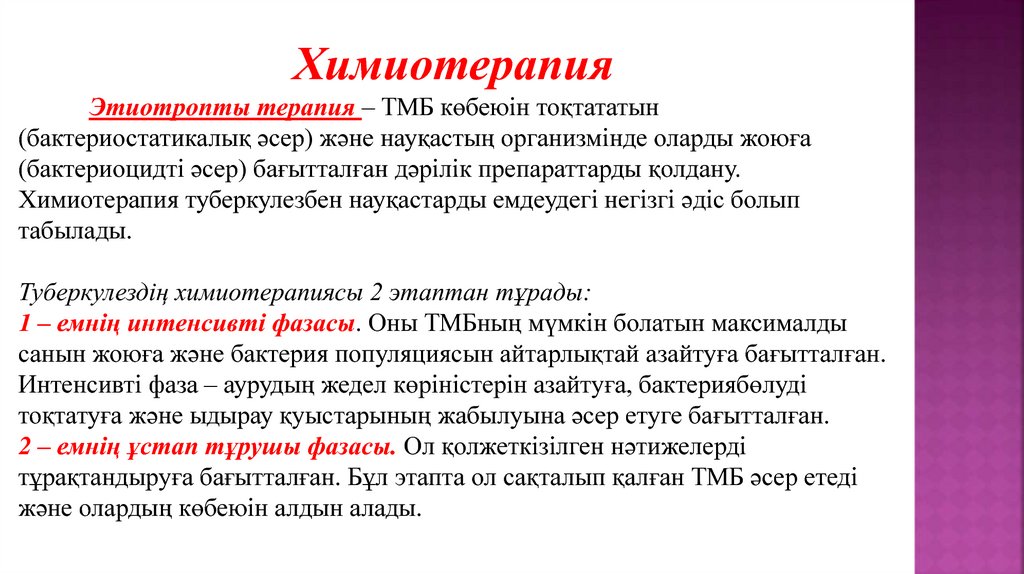

Лечение туберкулеза: Методики химиотерапии

Раздел: Визуальный дайджест